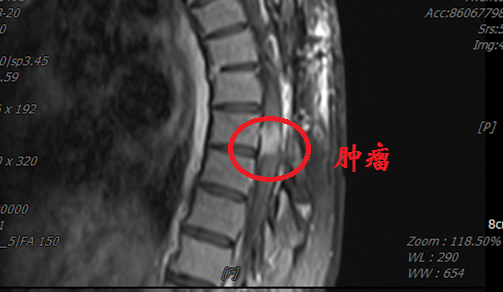

患者李女士(化名)来自西北少数民族地区,罹患胸段椎管内脊膜瘤,此前已在当地医院历经两次手术。近日,患她再次出现行走困难、疼痛难以平卧以及大小便费力,偶有失禁等症。患者首先回到最初就诊的省级医院,胸椎MRI示肿瘤再度复发,鉴于再次手术的难度和风险过高而被建议转院治疗。

几经辗转,患者来到西安交通大学第二附属医院神经外科就诊。郭振宇副主任医师接诊后,详细了解病情,发现“因多次手术,造成肿瘤与神经组织粘连严重,并且椎管腔内外解剖结构不清,再次手术患者瘫痪风险很高,并有可能大小便失禁”。